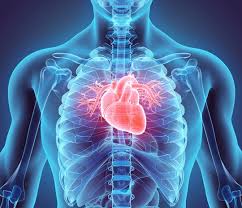

- 심장은 흉강(thorax) 중앙에 위치하며, 흉골(sternum) 바로 뒤, 좌측으로 살짝 치우쳐져 있습니다 :contentReference[oaicite:1]{index=1}.

- 정확히는 흉골 기준 좌측 2/3, 우측 1/3이 차지하며, 양쪽 폐 사이에 있는 중간격(mediastinum)에 포함돼 있습니다 :contentReference[oaicite:2]{index=2}.

- 흉부 2~5늑간(intercostal space) 사이, T5~T8 흉추 레벨로 위치하며, 척추와도 가까운 관계가 있습니다 :contentReference[oaicite:3]{index=3}.

3. 해부학적 표면 및 방향

- 앞 표면(sternocostal surface): 흉골 바로 뒤, 2~5늑간에 위치하며, 주로 우심실이 차지합니다 :contentReference[oaicite:7]{index=7}.

- 아래 표면(diaphragmatic surface): 횡격막 위에 위치하며, 좌심실이 주로 포함됩니다 :contentReference[oaicite:8]{index=8}.

- 폐측면(pulmonary surface): 좌폐와 접촉하는 좌심실 측면입니다 :contentReference[oaicite:9]{index=9}.

- 뒤면(base): 대정맥과 폐정맥이 연결되는 위치로, 심장의 뒷부분을 형성합니다 :contentReference[oaicite:10]{index=10}.

- 첨부(apex): 가슴왼쪽 5늑간선, 중선에서 약 9 cm 떨어진 곳에 위치하며, 좌심실 꼭대기를 형성합니다 :contentReference[oaicite:11]{index=11}.